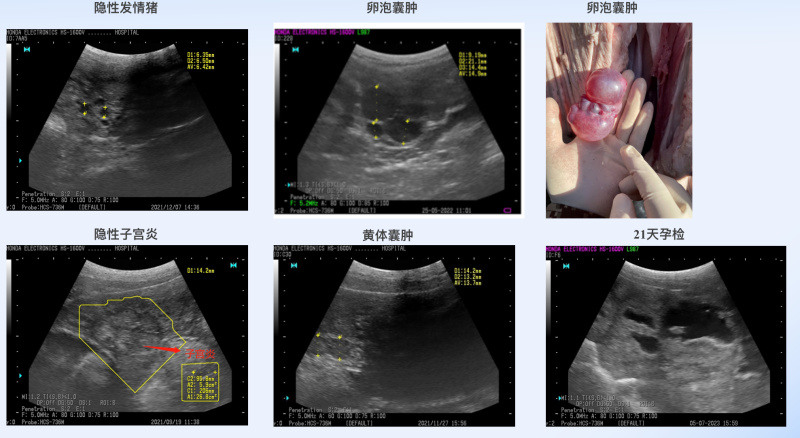

因此,伟杰信从国外引进先进的科研型B超,将B超影像技术引进卵泡发育和排卵研究,可视化监测母猪群卵泡发育和排卵规律,及时分析出最佳配种时机,为定时输精提供依据。B超除了监测卵泡发育和排卵规律,还可以用于对生殖系统状况的监测,如针对卵泡和黄体囊肿,隐性子宫炎症,子宫积脓积液的筛查,亦可用于20-21天早期测孕,预测产仔数等,可最大限度发挥母猪繁殖潜能,提高猪场生产成绩。

安静发情、隐性发情、发情异常猪处理

定时输精利器-B超的应用场景